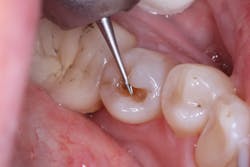

Most posterior teeth are a Vita shade A1/B1, an easy color to blend using many composites. The real test of a universal-shaded composite is its behavior in a darkly shaded posterior tooth. A lower bicuspid (tooth No. 20) with Vita shade C2 required removal of a defective amalgam restoration (figure 3). The site was not anesthetized; it was isolated using a DryShield, and the amalgam removed as a chunk using the Fissurotomy bur (figure 4).